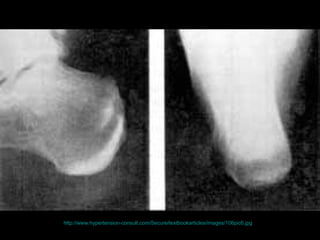

腳掌骨 ( 蹠骨 ) 之壓力性骨折 http://www.mikety.net/X-rays/Fx-mt.ANS.jpeg

http://www.hypertension-consult.com/Secure/textbookarticles/images/106pic6.jpg